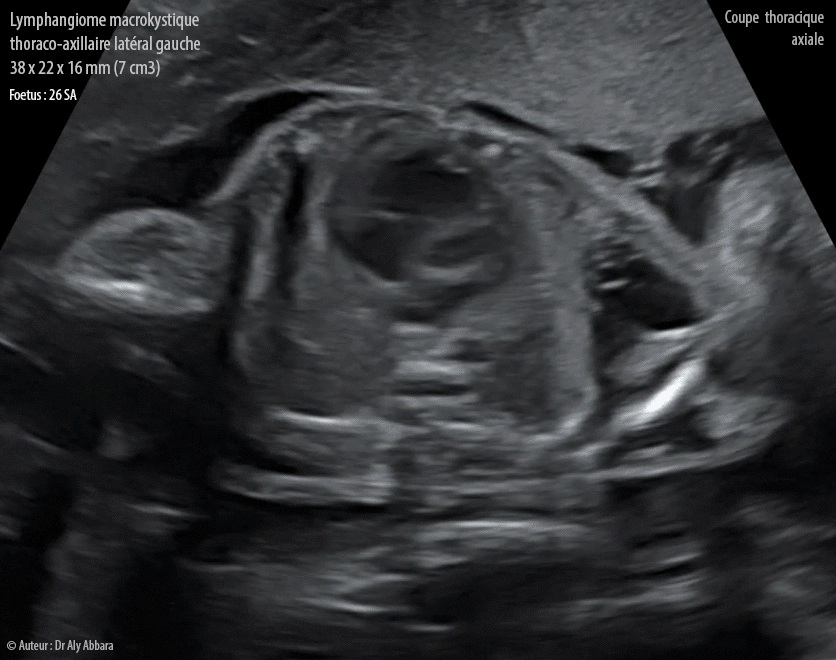

Lymphangiome macrokystique thoraco-axillaire gauche - Grossesse de 26 SA - Images échographiques en 2D

Lymphangiome thoraco-axillaire gauche :

• Séquence vidéo et auto diaporama (format GIF) d'images échographiques animées montrant un lymphangiome macropolykystique (sans composantes microkystiques), sous la peau, s'adossant la paroi extérieure latérale gauche de la cage thoracique avec extension sous axillaire, mais sans retentissement sur l'épaule proprement dite (sans d'atteinte articulaire). Écartement du bras gauche sous l'effet de masse exercé pas la tumeur.

Il s'agit d'un lymphangiome de 38 x 22 x 16 mm (soit 7 cm3).

• Pas d'extension en profondeur vers la cavité thoracique.

• Pas de composante vasculaire ni hémorragie interne (données de l'IRM à 32 SA).

• Pas d'autres anomalies morphologiques associées.

• Évolution in utero favorable et naissance à terme.